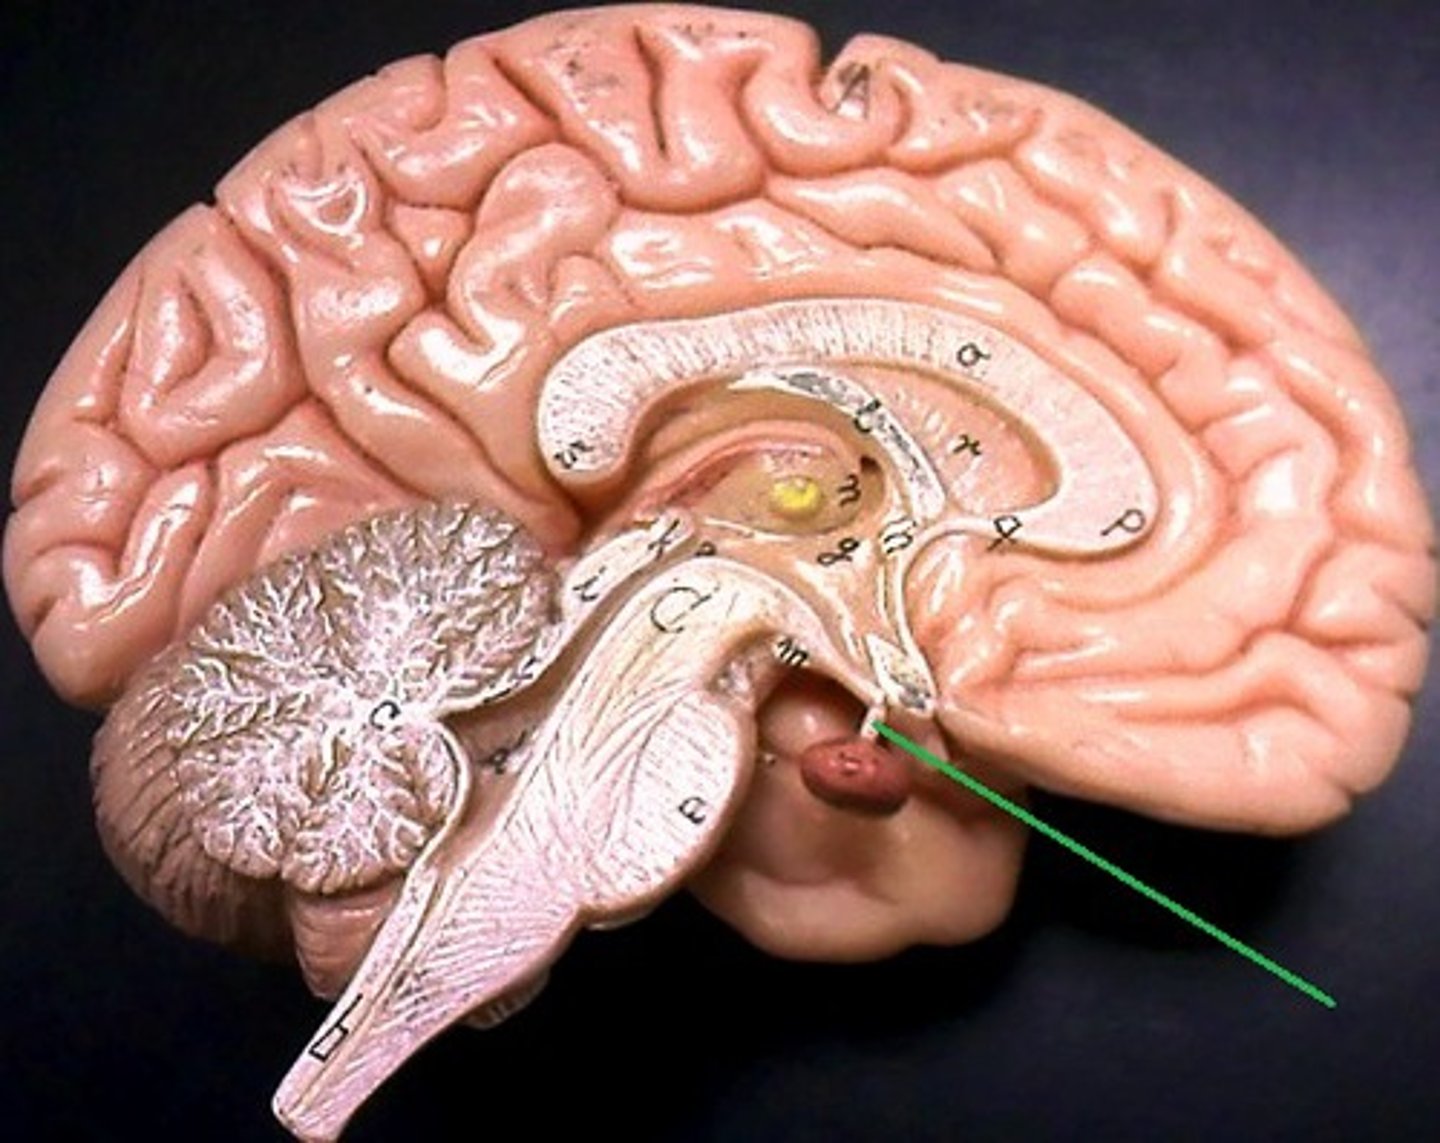

pituitary gland

the thing it hangs from is the infundibulum (the stalk that it hangs from. It regulates hormones. Releases hormones that control other endocrine glands. Releases tropic hormones.

infundibulum

The stalk that the pituitary gland hangs from.

mammillary bodies

two bumbs between pituitary gland and brain stem. Part of limbic system. Contributes to functioning of limbic system.

pineal body

considered an endocrine gland. Secretes melatonin. Plays a role in circadian rhythm - regulation of this. Sleep/wake cycles or night/day cycles. They don't know exactly how this works, but if the pineal gland does not release melatonin, you can have differences in circadian rhythm.

brain stem

Includes the mid brain, pons, and medulla oblongata.

midbrain

corpora quadrigemina,connector of cerebrum, diencephalon, and cerebellum to spinal cord. Connector in central nervous system.

corpora quadrigemina

Also known as the tectal plate. Consists of the superior colliculi and the inferior colliculi.

superior colliculi

bumby part on opposite side of pituitary gland. Top one. Responsible for visual reflex (track objects visually). If we see something in peripheray, we can turn towards object. Instinctive reflex.

inferior colliculi

bumpy part on opposite of pituitary gland. Bottom one. 31 auditory tracking. If we hear a loud noise, we can move toward it.

pons

contains parts of respiratory center. Plays a role in controlling breathing rate and depth.

medulla oblongata

has a cardiac center. Plays a role in influencing heart rate and the force of the contractions in the heart. In response to changes in blood pressure and oxygen levels.

- vasomotor center - helps to control blood pressure. Sends out signals that causes vasoconstriction or vasodilation of blood vessels. Contains parts of respiratory center.

- initiates inspiration and respiration.

cerebellum

cerebellar hemispheres, cerebellar cortex, and arbor vitae.-

the little brain.

- Function: coordinates all voluntary movements. Ability to ride a bike, dance, anything complicated that calls for coordinating movement between left and right sides with skeletal muscles.

- Ability to move joints in a coordinated fashion- cerebellum in charge.

ventricles

cavities in the brain. Includes lateral ventricles - right and left, third ventricle, fourth ventricle, cerebral aqueduct, and choroid plexus.

lateral ventricles (left and right)

right and left. Actual open space. Behind the corpus collosum.

- Cerebrospinal fluid circulates through these ventricles and underneath the meninges.

- Gives the brain buoyancy.

- brain floats a little bit and this prevents trauma.

third ventricle

in the area where the hypothalamus is.

fourth ventricle

located beneath the arbor vitae in the cerebellum.

cerebral aqueduct

connector between third and fourth ventricle in front of colliculi.

choroid plexus

ependymal cells - line ventricles and central canal of spinal cord.